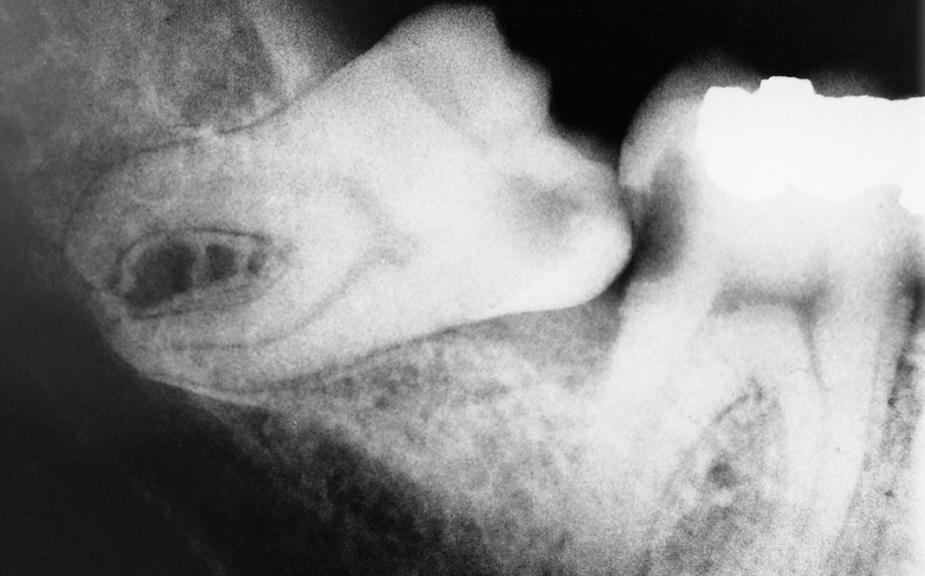

Prevention of Odontogenic Cysts and Tumors

When impacted teeth are completely within the alveolar process, the associated follicular sac is also frequently retained. Although the dental follicle maintains its original size in most patients, it may undergo cystic degeneration and become a dentigerous cyst. If the patient is closely monitored, the dentist can diagnose the cyst before it reaches large proportions ( Fig. 10.11 ). However, unmonitored cysts can reach enormous sizes ( Fig. 10.12 ). As a general guideline, if the follicular space around the crown of the tooth is greater than 3 mm, the preoperative diagnosis of a dentigerous cyst is reasonable.

Fig. 10.11, Small dentigerous cyst arising around an impacted tooth.

Fig. 10.12, Large dentigerous cyst that extends from the coronoid process to the mental foramen. The cyst has displaced the impacted third molar to the inferior border of the mandible.